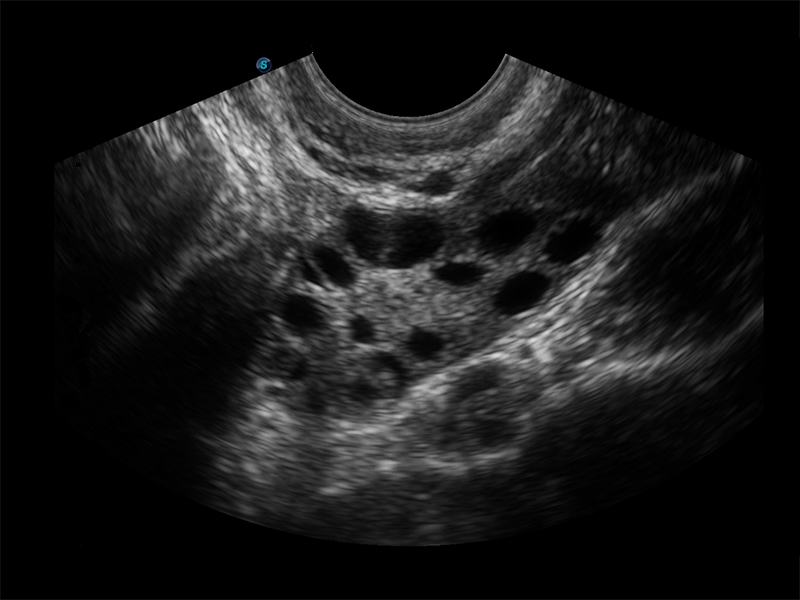

Độ phân giải cao và sắc nét của hình ảnh trên máy siêu âm Sonoscape E3

Ứng dụng thăm khám: Ổ bụng, sản khoa, niệu khoa, tim mạch, nhi khoa, bộ phận nhỏ, mắt, phần nông, tuyến giáp, tuyến vú, phụ khoa, mạch vành, dây thần kinh ngoại biên, cơ xương khớp, giảm đau/ gây mê, cấp cứu... Máy được thiết kế dạng xách tay mỏng nhẹ 5.5kg, có quai xách, pin dự phòng sẵn, 2 đầu dò tiêu chuẩn Convex và linear.